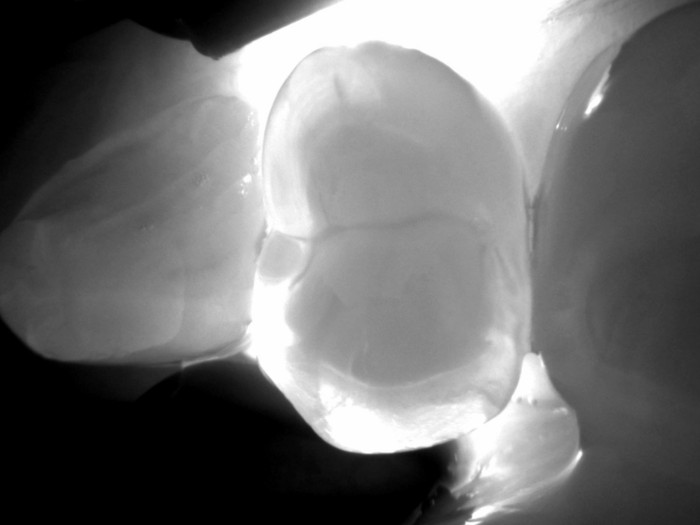

Die DIAGNOcam Vision Full HD verwendet für diesen Prozess Nah-Infrarot-Beleuchtung (NIR) anstelle von weißem Licht. Auf den Produktfotos können Sie sehen, das zwei kleine Arme am Gerät zu sein scheinen. Diese Arme werden über den Zahn geführt, um ihn von der bukkalen und lingualen Seite zu umschließen, und sie enthalten Glasfasern, die das NIR-Licht von beiden Seiten des Zielzahns abgeben. NIR dringt unschädlich und effektiver in den Zahn ein als weißes Licht und ohne Lichtverschmutzung. Diese Bilder sind genauso klar wie die intraoralen Bilder und können dem Patienten zur Erläuterung der Befunde vorgelegt werden.

Die Transillumination ist ein großartiges Instrument zum Auffinden von Läsionen, die zu klein sind, um auf Röntgenbildern erkannt zu werden. Sie ist ein hervorragendes Hilfsmittel für die Frühdiagnose, die Kinderheilkunde und schwangere Patienten. Sie ist auch ein hervorragendes Instrument zur Überwachung der Remineralisierungstherapie.

Die Transillumination ist auch ein nützliches Instrument zur Lokalisierung von Rissen in Zähnen und Karies unter Versiegelungen und Restaurationen. Für konservative Ärzte ist dieses Produkt eine wunderbare Ergänzung für ihre Patienten.